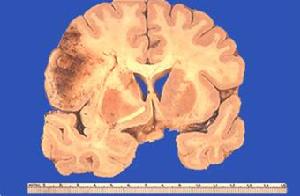

中樞神經系統1.中樞神經系統NCL表現為具有黃色自發螢光特性的脂色素,廣泛沉積在神經細胞和其他細胞的胞質內,從而導致神經的氣球樣腫脹,和以大腦皮質及視網膜為主的神經細胞脫失病變,在不同的亞型存在明顯的差異,在嬰兒型和晚期嬰兒型,NCL大腦和小腦皮質的神經細胞脫失很完全,這些改變導致大腦皮質的顯著萎縮和半卵圓中心的有髓神經纖維脫失,脂色素出現在膠質細胞和血管上,皮細胞內晚期嬰兒型NCL的病理改變在不同患者間存在較大的變異,在晚期嬰兒型NCL的Wisniewski變異型出現廣泛的腦萎縮,腫脹的神經細胞主要出現在齒狀核-黑質-紋狀體-丘腦區域,較少出現在大腦皮質。而NCL的色素變異型的中央灰質可見軸突球形成。一例晚期嬰兒型NCL的中央灰質和腦皮質可以同等程度受到明顯的累及,而且腫脹的神經細胞突起也出現在小腦分子層內。

在青少年型NCL神經細胞的脫失不很顯著主要是第Ⅱ層的小神經細胞的喪失,100µm的厚片顯示小神經細胞的喪失和脂色素在神經細胞核周體的出現以皮質Ⅲ和Ⅴ層更明顯,其他神經細胞可以大量存在成年型NCL的神經細胞脫失也不明顯主要表現為皮質和基底核的累及,這些改變常合併有軸突近端的脂色素增加形成軸突的梭形腫脹。北方癲癇型的大腦皮質病理改變也比較輕微小腦沒有明顯的病理改變。